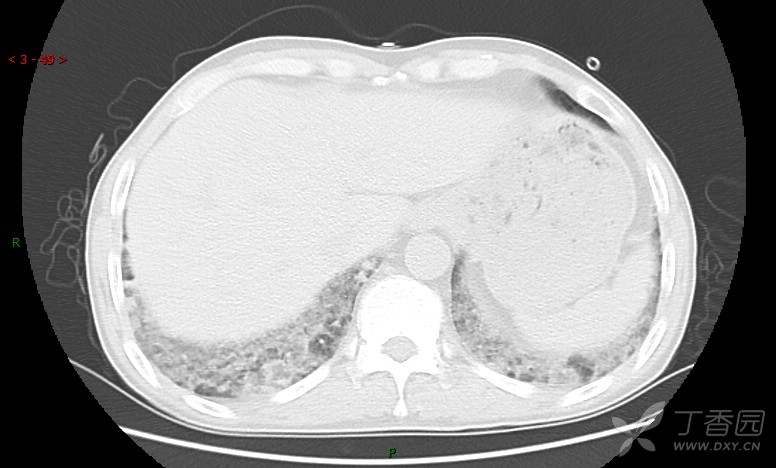

地图+铺路石征=PAP?那升高的CEA怎么说(病例3连发,附其他2例链接)

患者男,42岁,咳嗽半年余,加重伴憋喘2月余。

血清肿瘤相关抗原116.22U/ml↑(0--95);

癌胚抗原 61.96 ng/mL ↑ 0--5

神经特异性烯醇化酶 33.12 ng/ml ↑ 0--16.3

细胞角蛋白19片段测定 40.23 ng/ml ↑ ≤3.3